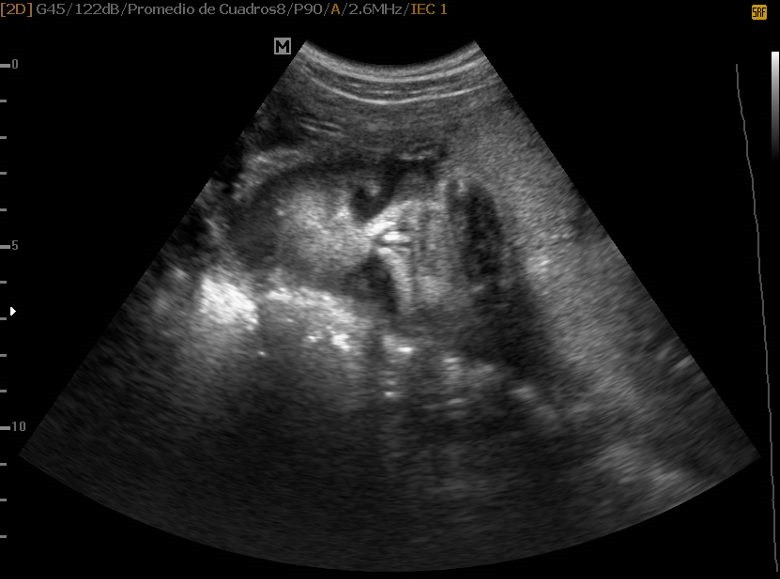

Varias ultrasonografías en 2D y 3D

Envíado por Dr. Nelson Menjívar Sarco